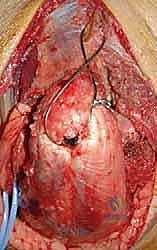

With the nerve protected, attention turns to the olecranon osteotomy. A chevron-shaped osteotomy, with the apex pointing distally, is preferred over a transverse cut as it provides inherent rotational stability and a larger surface area for healing. The osteotomy site is targeted at the bare area of the greater sigmoid notch, typically 2-3 centimeters distal to the olecranon tip. Crucially, before initiating the cut, the proximal ulna is pre-drilled and tapped for a 6.5mm or 7.3mm cannulated lag screw to ensure perfect alignment during subsequent repair. The osteotomy is initiated with a fine oscillating saw and completed with a thin osteotome to crack the subchondral bone, preserving the articular cartilage interdigitation. The olecranon fragment, with the triceps mechanism attached, is then reflected proximally, granting a breathtaking, 360-degree view of the distal humeral articular surface.

The fracture reduction sequence follows a strict "inside-out" and "bottom-up" philosophy. The primary objective is the anatomical restoration of the articular block (the "tie"). The trochlear and capitellar fragments are meticulously debrided of hematoma, reduced using pointed reduction forceps, and provisionally stabilized with smooth Kirschner wires. This articular assembly is then definitively fixed using headless compression screws or countersunk cortical lag screws, ensuring no hardware violates the joint surface. Once the articular block is reconstituted into a single, solid unit, it is reduced to the medial and lateral columns of the humeral diaphysis. Provisional fixation to the shaft is achieved with K-wires, and orthogonal fluoroscopy is utilized to confirm anatomical alignment, particularly the crucial 30-degree anterior tilt of the articular surface.